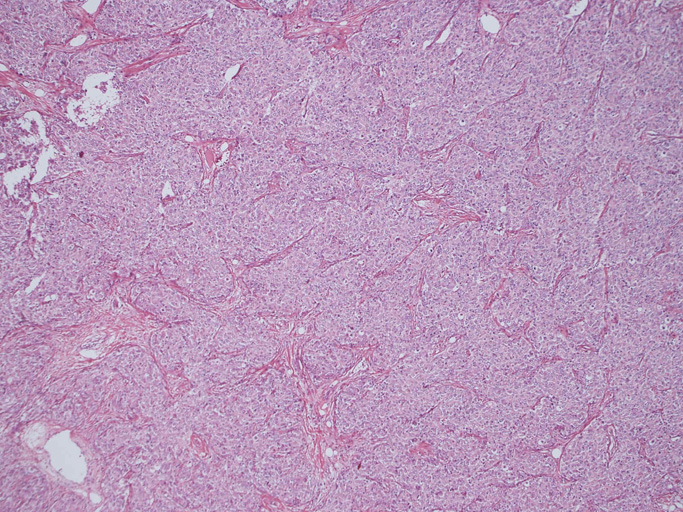

腫瘍は, 細血管を含む細い線維組織束で分画された胞巣状充実性病変で(Fig01),類円形ないし卵円形のvesicularな核をもつ円形, 多稜形の細胞が増殖している。核小体は小型, やや不明瞭。細胞質は境界が不鮮明で好酸性泡沫状を呈するものが多い。大型核やbizzarreな核の出現も認められる(Fig02-05)。血管周囲にリンパ球浸潤が認められる部分がある(Fig06,07)。